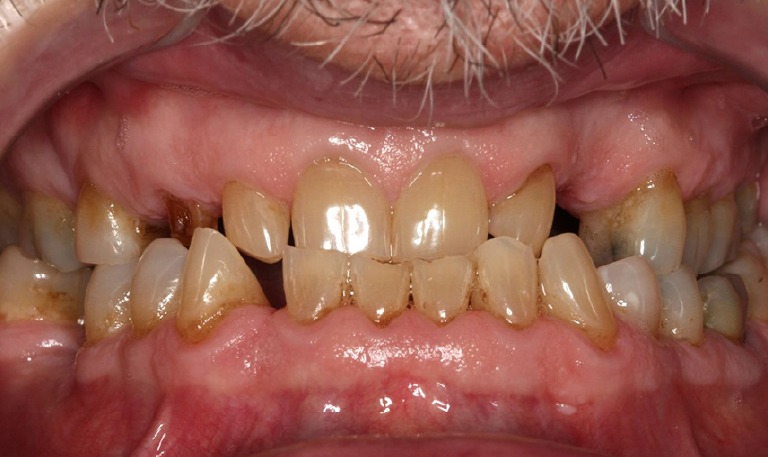

Caso de Rehabilitación completa y aumento de DV

BeforeAfter